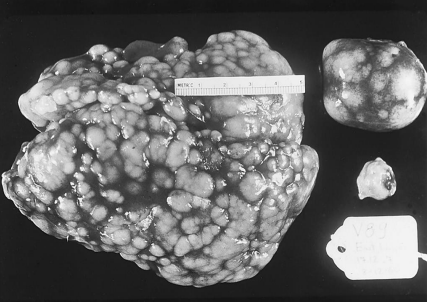

• subgroup J는 myelocytic myeloid leukosis a& renal adenomas, 그 외 마이너한 종양 유발 (A~E와는 조금 다름) (같은 liver tumor지만, tumor가 일어난 cell의 종류에 따라 3가지로 구분됨(lymphoid, erythrocyte, myelocyte) (왼쪽이 liver. 간에서 diffuse tumor가 나타남. 오른쪽은 spleen-focal tumor) (총배설강의 tumor에서는 거대한 nodule이 관찰됨)